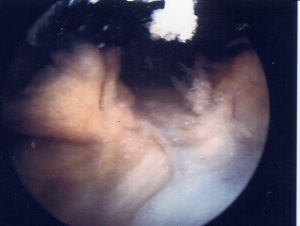

Abb.7 intraoperativer Situs einer spezifischen hyperplastisch-zottigen Synovialitis

Beim Rheuma (Abb.7) finden sind zusätzlich lymphatische Follikel oder vergleichbare lymphozytäre Aggregate, bestehend aus B-Lymphozyten, T-Lymphozyten und Netzwerken mit perivaskuläre Infiltraten aus T-Zellen und Monozyten. Ortsständige Fibroblasten unterstützen Gedächtniszellen bei der Differenzierung zu Plasmazellen sowie die Produktion von TNFα, IL-1, 6, 8 u.a. Die Invasion von Entzündungszellen (Abb.8) wird über oben genannte Zytokine und aktivierte Komplementfaktoren gefördert. Antikörper von B-Zellen werden in Serum und Synovia gefunden. [4,5]